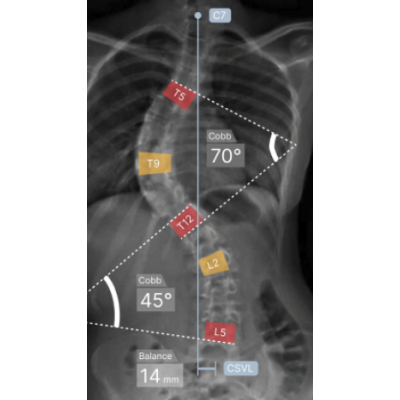

AZmeasure delivers automatedcharacterization of osteo-articulargeometries, includinglengths andangular positions.

Scoliosis